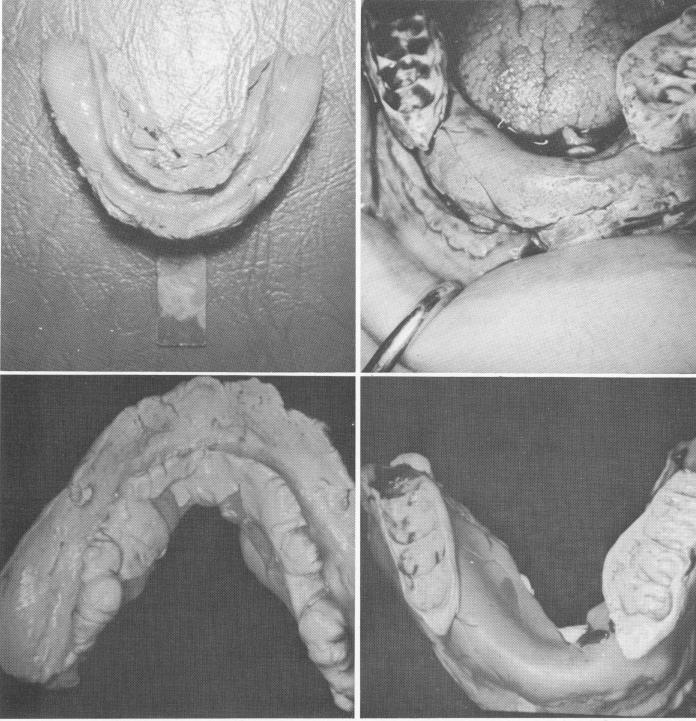

Aside from the surgery, the most important first step toward a successful subperiosteal implant is making an accurate impression including each and every imperative anatomic landmark. These landmarks are both external oblique ridges, both neurovascular bundles exiting the mental foramina, both mylohyoid ridges, the genial tubercles, and the symphysis. The importance of these landmarks cannot be stressed enough, for without the dense bone in these areas to support the metallic framework, no implant could ever be successful.

Fig. 12-18. A, The rubber impression was taken of the exposed bone that included the external oblique ridges, symphysis, genial tubercles, mylohyoid ridges, the neurovascular bundles exiting the mental foramina. B, The implant (silicone putty) impression is taken of the exposed mandible in heavy-bodied material. C, A light wash material is used for finer details. D, A silicone wash bite is taken directly over the heavy-bodied tray while it is still in the mouth.